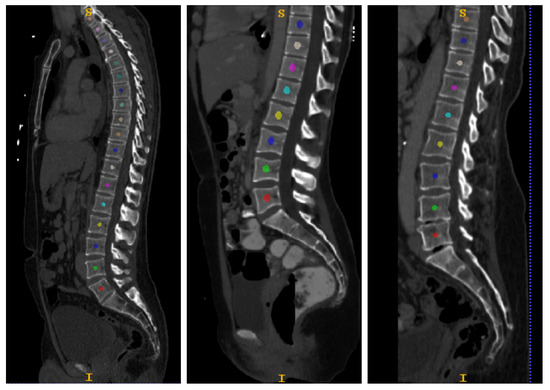

- Centroids’ Computation and Slice Showing. If the output vertebrae number matches with the input number from the first step, the algorithm goes further with the computation of centroids’ positions for each vertebra; otherwise, the process has to be repeated from another slice.

- Best Slice Selection and Centroids’ Storage. The algorithm repeats the workflow until it reaches a slice without connected components. Then, the user chooses the best slice among the showed ones, and the algorithm stores the centroids’ position.

- 3D Multi-class Segmentation. Centroids are used in a k-nearest neighbors (k-NN) classifier to produce a 3D segmentation map in which each vertebra has its own label.